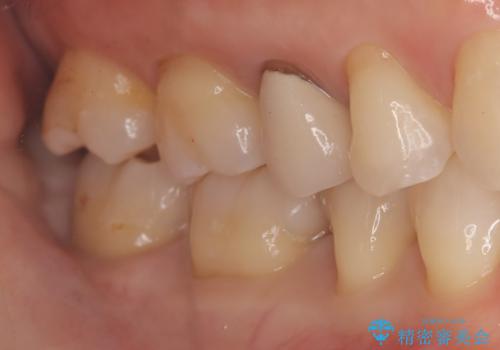

- 主訴:下の歯に入っている銀歯が笑うと目立つので白くしたい。

下顎臼歯部に入っている保険適用のメタルインレー(4箇所)を、審美性・適合性・清掃性の良いセラミックインレーにてやり替えました。